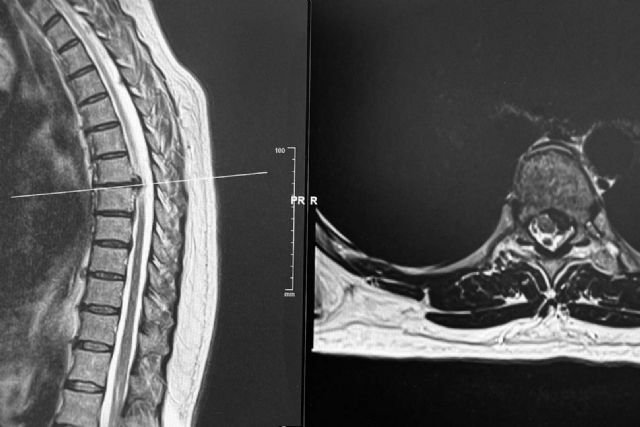

Los discos dorsales son tejidos semejantes a un cojín esponjoso que se encuentran entre las vértebras de la columna. Las hernias aparecen cuando uno de los discos sobresale de entre las vértebras, presionando los nervios y la médula, lo que produce dolor y otros síntomas como la sensación de hormigueo, dependiendo del lugar en el que se originen.

Es común que con la edad, el material gelatinoso que amortigua los discos se debilite y desaparezca, posibilitando movimientos que los desvíe de su posición original, produciendo de esta manera una hernia. Cuando el disco llega a presionar la médula o algún otro nervio importante, es posible que el paciente presente sensación de adormecimiento en las extremidades y, en casos más graves, debilidad en las extremidades o dificultad para el movimiento.

Existen diferentes maneras de detectar una hernia discal, pero en todo caso, es el especialista médico el que debe valorar al paciente y especificar el método de diagnóstico que mejor se adapte a sus necesidades y a la naturaleza de su lesión. El tratamiento dependerá de la gravedad de la hernia. Por regla general, el tratamiento es inicialmente conservador con el uso de medicamentos, reposo, rehabilitación e infiltraciones en su caso.